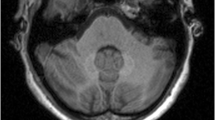

In patients with RRMS, SI within the dentate nucleus and globus pallidus increased on unenhanced T1-weighted images after multiple gadobutrol injections. Administration of the same total amount of gadobutrol over a shorter period caused greater SI increase.

• Gadolinium deposition may occur within the human brain after multiple gadolinium contrast administrations

• Increasing T1W signal intensity occurs within the dentate nucleus and globus pallidus

• Increasing signal intensity may be a consequence of multiple administrations of gadobutrol

• Administration of gadobutrol over a shorter period causes greater signal intensity increase